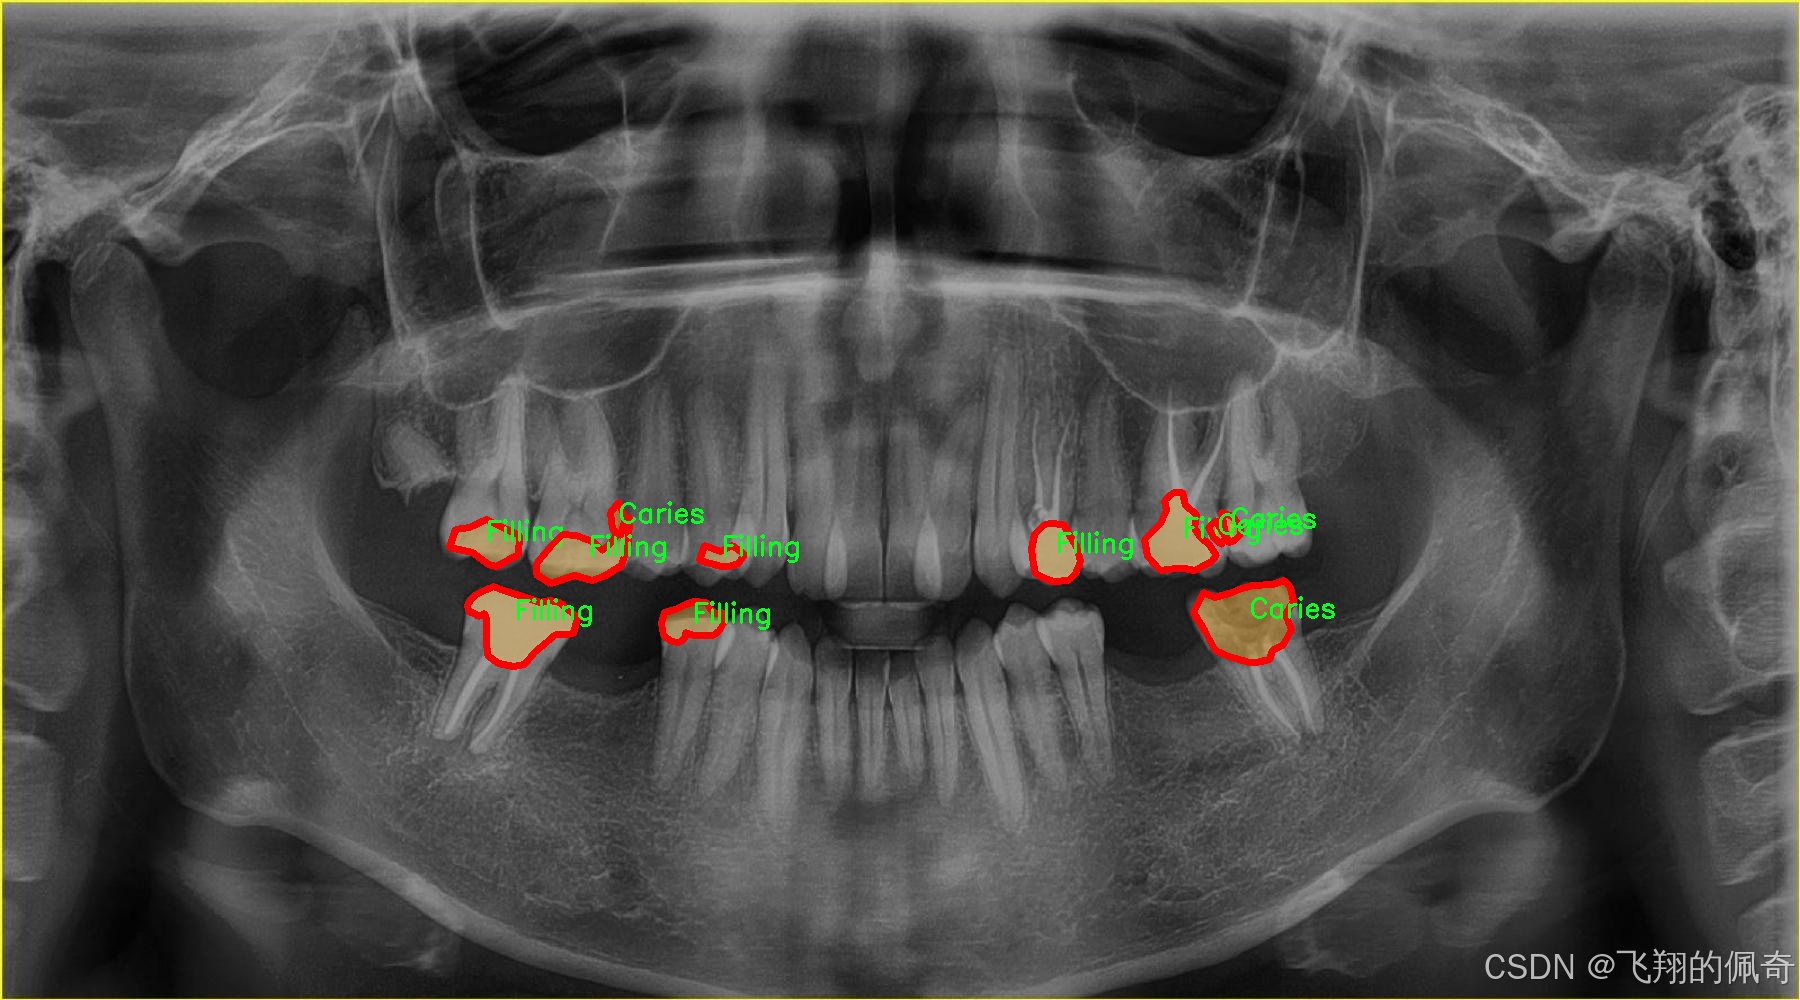

图片效果

在现代牙科医学中,龋齿的早期诊断与治疗至关重要,而图像分割技术在这一领域的应用为牙科医生提供了更为精确的工具。为此,我们构建了一个名为“tooth segmentation”的数据集,旨在训练改进版的YOLOv8-seg模型,以实现对牙齿病变图像的高效分割。该数据集专注于八种不同的牙齿病变类型,涵盖了从龋齿到各种修复体的多样性,确保模型能够识别和分割这些关键特征。

“tooth segmentation”数据集包含八个类别,分别为:龋齿(Caries)、牙冠与桥(Crown-Bridge)、填充物(Filling)、植牙(Implant)、后螺钉(Post-screw)、根管填充(Root canal Obturation)、牙冠(crown)以及再植体(implant)。这些类别不仅代表了牙齿的不同病变状态,还涵盖了牙科治疗中常见的修复和重建过程。这种多样性使得数据集在训练过程中能够有效地提高模型的泛化能力,帮助其在实际应用中更好地适应不同的病例。